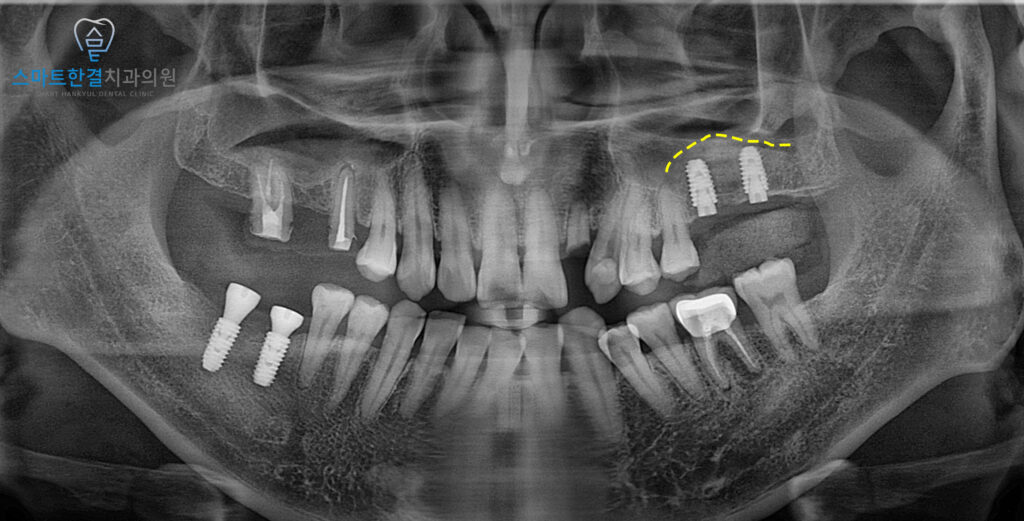

측방으로 접근하여

잇몸뼈를 조심스럽게 열고,

상악동 막을 들어 올린 뒤

그 공간에 인공뼈를 이식하는

과정을 진행했어요.

이를 통해 임플란트를

안정적으로 식립 할 수 있는

충분한 골량을 확보할 수 있었어요.